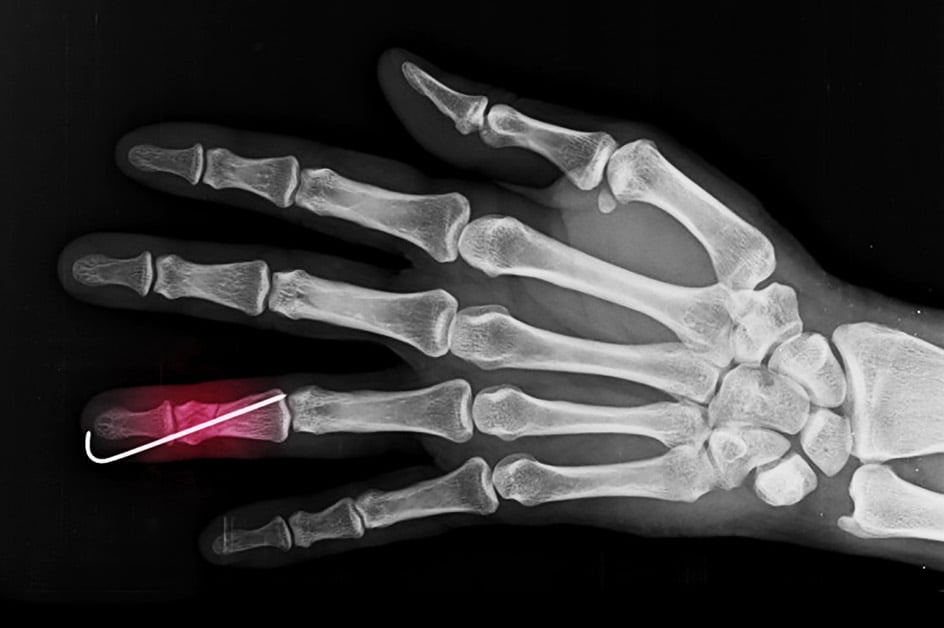

X-ray showing pinning in a finger to repair a Phalanx Fracture

Surgical repair of phalanx fractures is required when the fracture pieces are unstable (won’t stay in place), or not healing properly with splint treatment. We give a mild sedation and a local block to numb the finger in the operating room. If the phalanx can be set straight, we place metal wires through the skin and into the bone to keep it straight while it is healing. If the fracture is severe, we may need to make a small incision over the finger to restore the alignment of the broken phalanx directly and hold the pieces in place with tiny metal plate and/or screws. Often, a second surgery is performed after the bone has healed to remove the plate and screws if they are uncomfortable under the skin or cause finger stiffness.